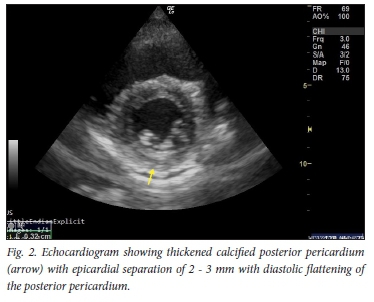

Case 2 was a fit woman in her thirties, with no previous medical history. She contracted mild COVID-19 pneumonia in July 2020, for which she was treated at home. Her course was uncomplicated and she recovered well. About one month later she started jogging again, and soon noticed that exertion brought on significant dyspnoea and pleuritic chest pain. She consulted her general practitioner, who did not find any clinical or ECG abnormalities and referred her to GC's practice for an echocardiogram. This documented the presence of a small posterior pericardial effusion, probably related to COVID-19 infection (Fig. 2).

Cardiac complications of COVID-19 include myocardial injury, myocarditis, acute myocardial infarction, heart failure, dysrhythmias, pericarditis and venous thromboembolic events.[1] The prevalence is unclear, but acute myocarditis may account for up to 7% of deaths. It may present with a variety of symptoms including chest pain, dyspnoea, dysrhythmia, and acute left ventricular dysfunction with cardiogenic shock. Serum troponin values are generally abnormal. The ECG can demonstrate a range of findings including nonspecific ST-segment-T-wave abnormalities, T-wave inversion, PR-segment and ST-segment deviations (depression and elevation) and ventricular arrhythmias. The echocardiogram may be helpful in distinguishing pericarditis from acute myocardial infarction. The likely pathophysiology is a combination of the direct viral insult to cardiomyocytes, the immune response to virally infected myocardium, and drugs that prolong the QT interval.[2]

Case 2 represents another cardiac complication of COVID-19, namely pericarditis.[4] She typically presented with pleuritic chest pain. Pericarditis is usually mild, but may occasionally be associated with significant pericardial effusion and tamponade requiring therapeutic pericardiocentesis.[5] It can be present at the time of the initial diagnosis or occur later in the course of the disease. The appearance of an increased cardiac silhouette on the chest radiograph and typical features of ST elevation on the ECG may suggest pericarditis/pericardial effusion, which can usually be confirmed by transoesophageal echocardiography or a computed tomography (CT) scan.